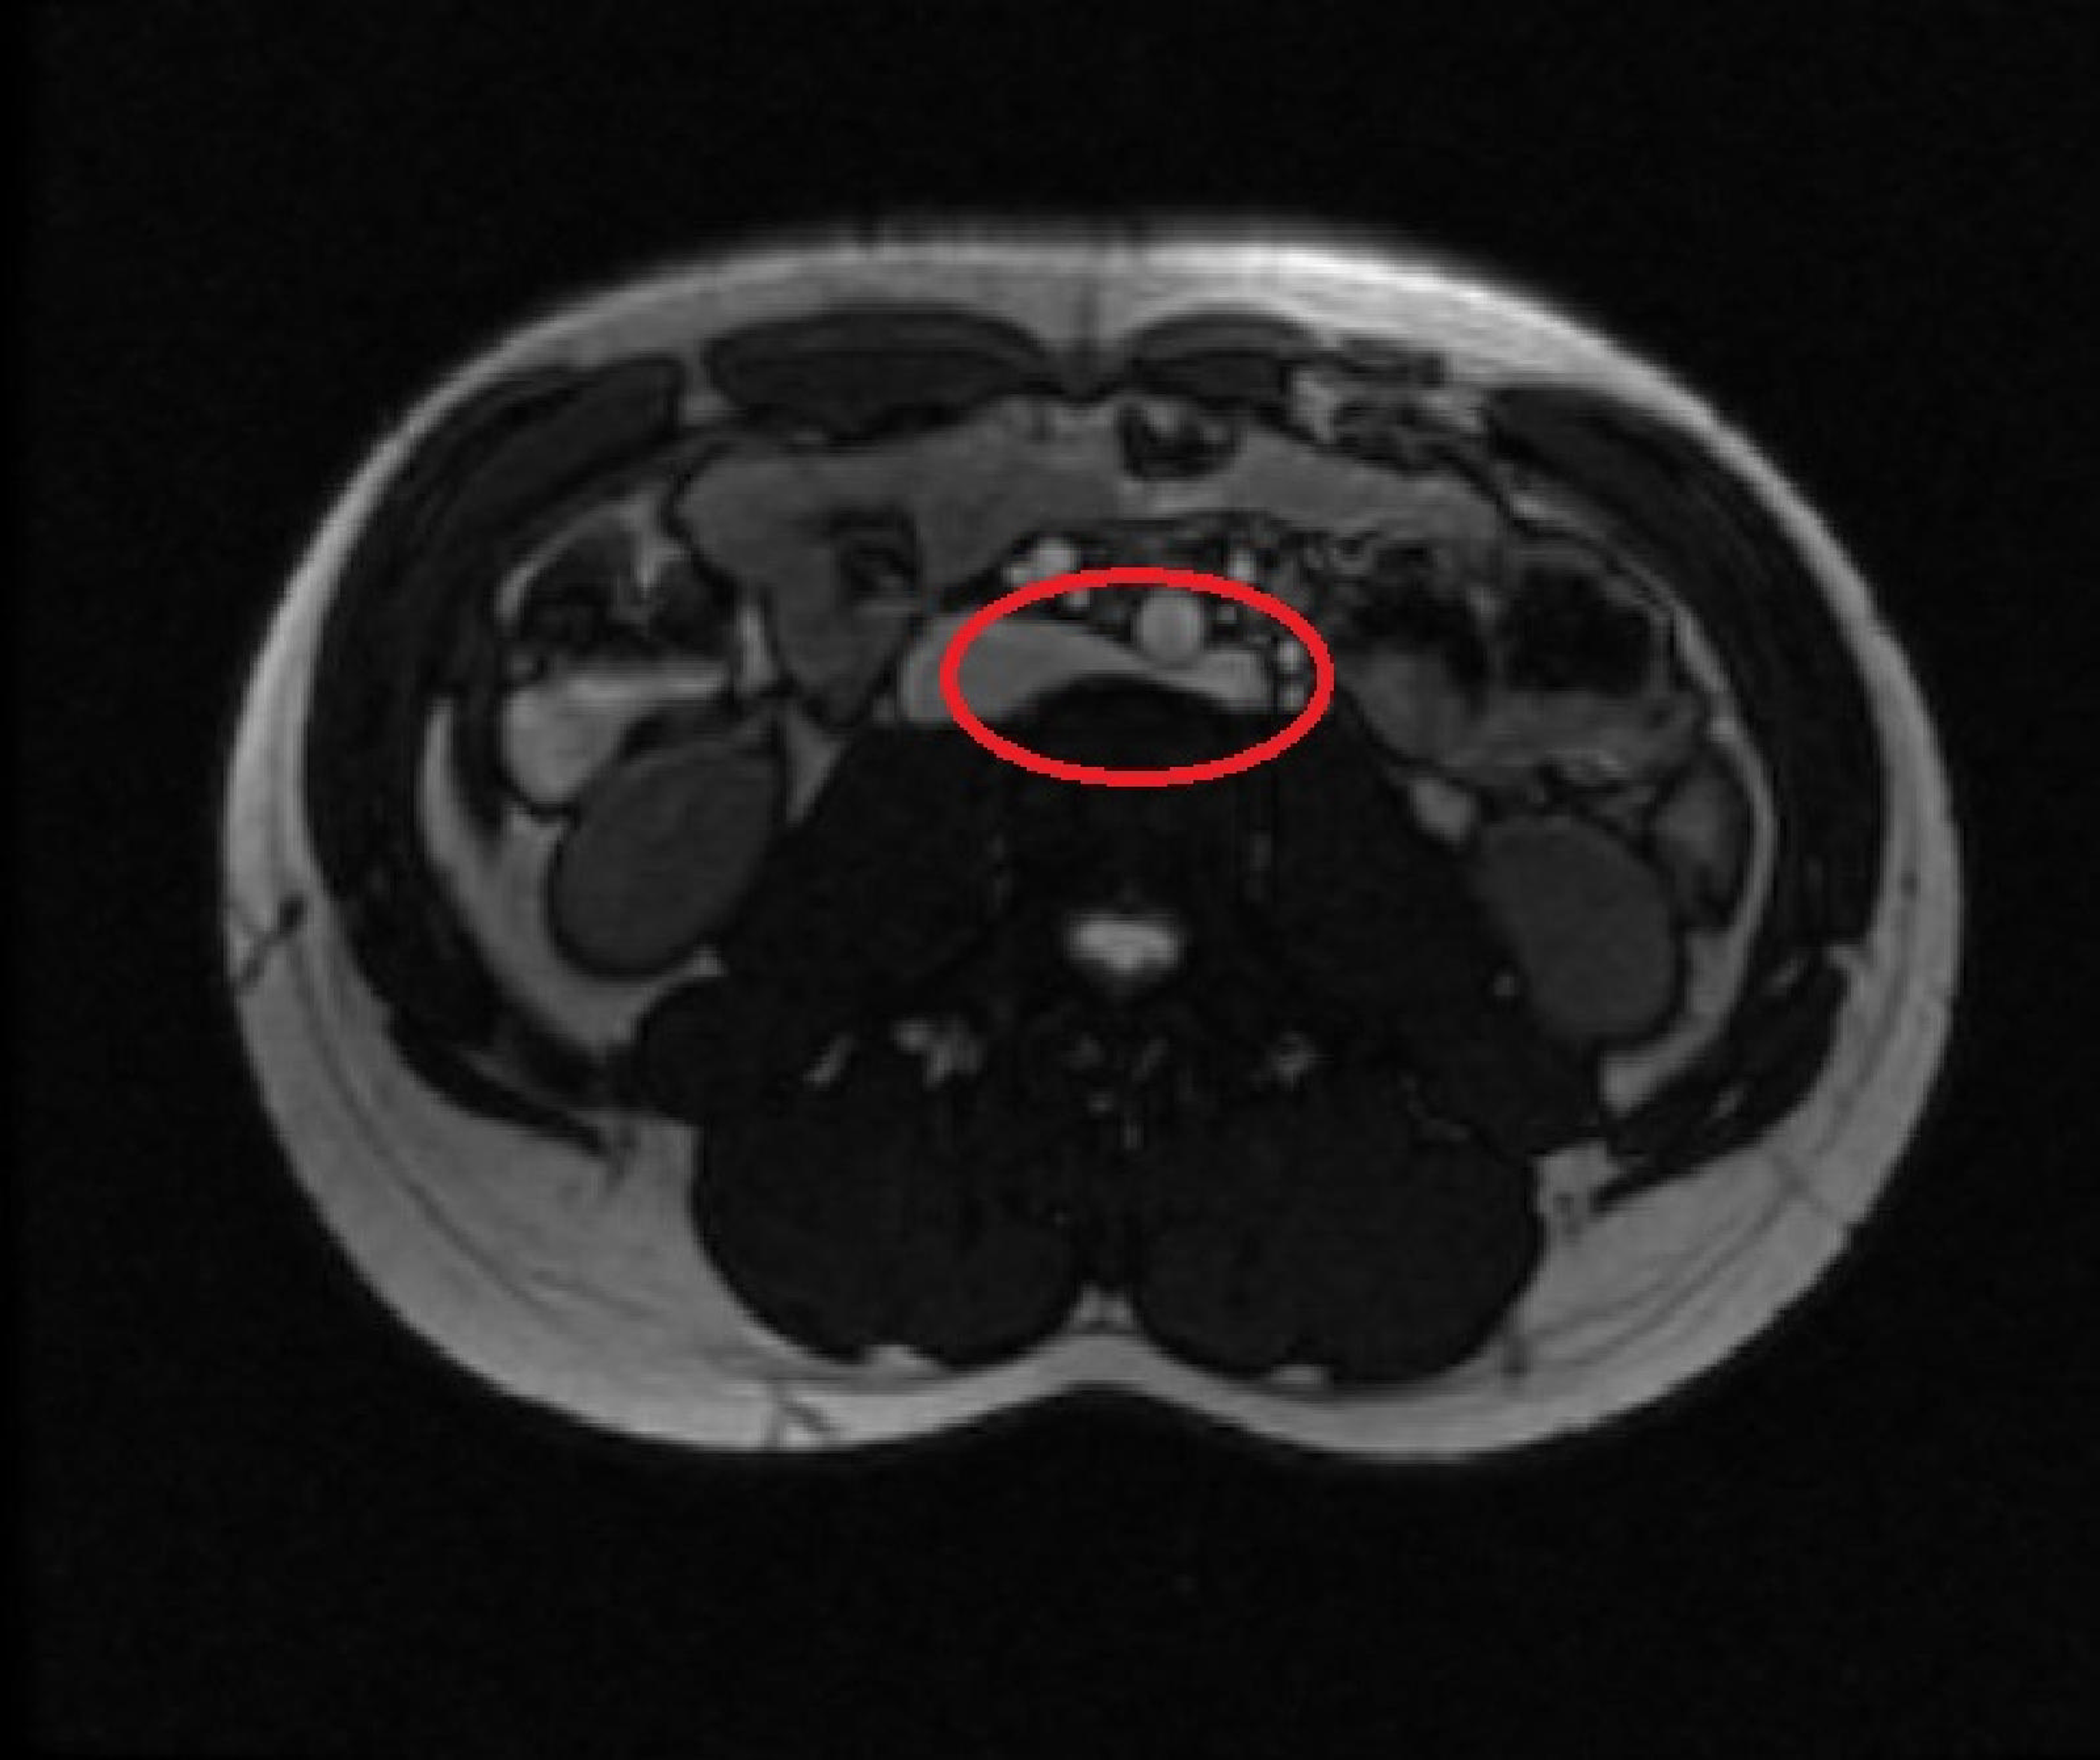

Nutcracker Syndrome Male . Nutcracker syndrome is a vascular compression disorder that refers to the compression of the left renal vein, most commonly between the superior. Nutcracker syndrome is a vascular compression disorder when two arteries pinch the left renal vein, which carries blood from the left kidney back to the heart. It occurs when arteries, most often the abdomen’s aorta and superior mesenteric. Nutcracker syndrome is a rare vein compression disorder. Nutcracker syndrome may contribute to infertility in. Nutcracker phenomenon is a vascular condition where there is compression of the left renal vein most commonly between the aorta and superior. In nutcracker syndrome, symptoms are most often caused when the left renal vein coming from the left kidney becomes compressed and blood can’t flow normally through it.

Nutcracker syndrome on ultrasound. r/Radiology Nutcracker Syndrome Male Nutcracker phenomenon is a vascular condition where there is compression of the left renal vein most commonly between the aorta and superior. It occurs when arteries, most often the abdomen’s aorta and superior mesenteric. Nutcracker syndrome is a vascular compression disorder that refers to the compression of the left renal vein, most commonly between the superior. In nutcracker syndrome, symptoms. Nutcracker Syndrome Male.

Nutcracker syndrome Image Nutcracker Syndrome Male Nutcracker phenomenon is a vascular condition where there is compression of the left renal vein most commonly between the aorta and superior. In nutcracker syndrome, symptoms are most often caused when the left renal vein coming from the left kidney becomes compressed and blood can’t flow normally through it. Nutcracker syndrome is a rare vein compression disorder. Nutcracker syndrome is. Nutcracker Syndrome Male.